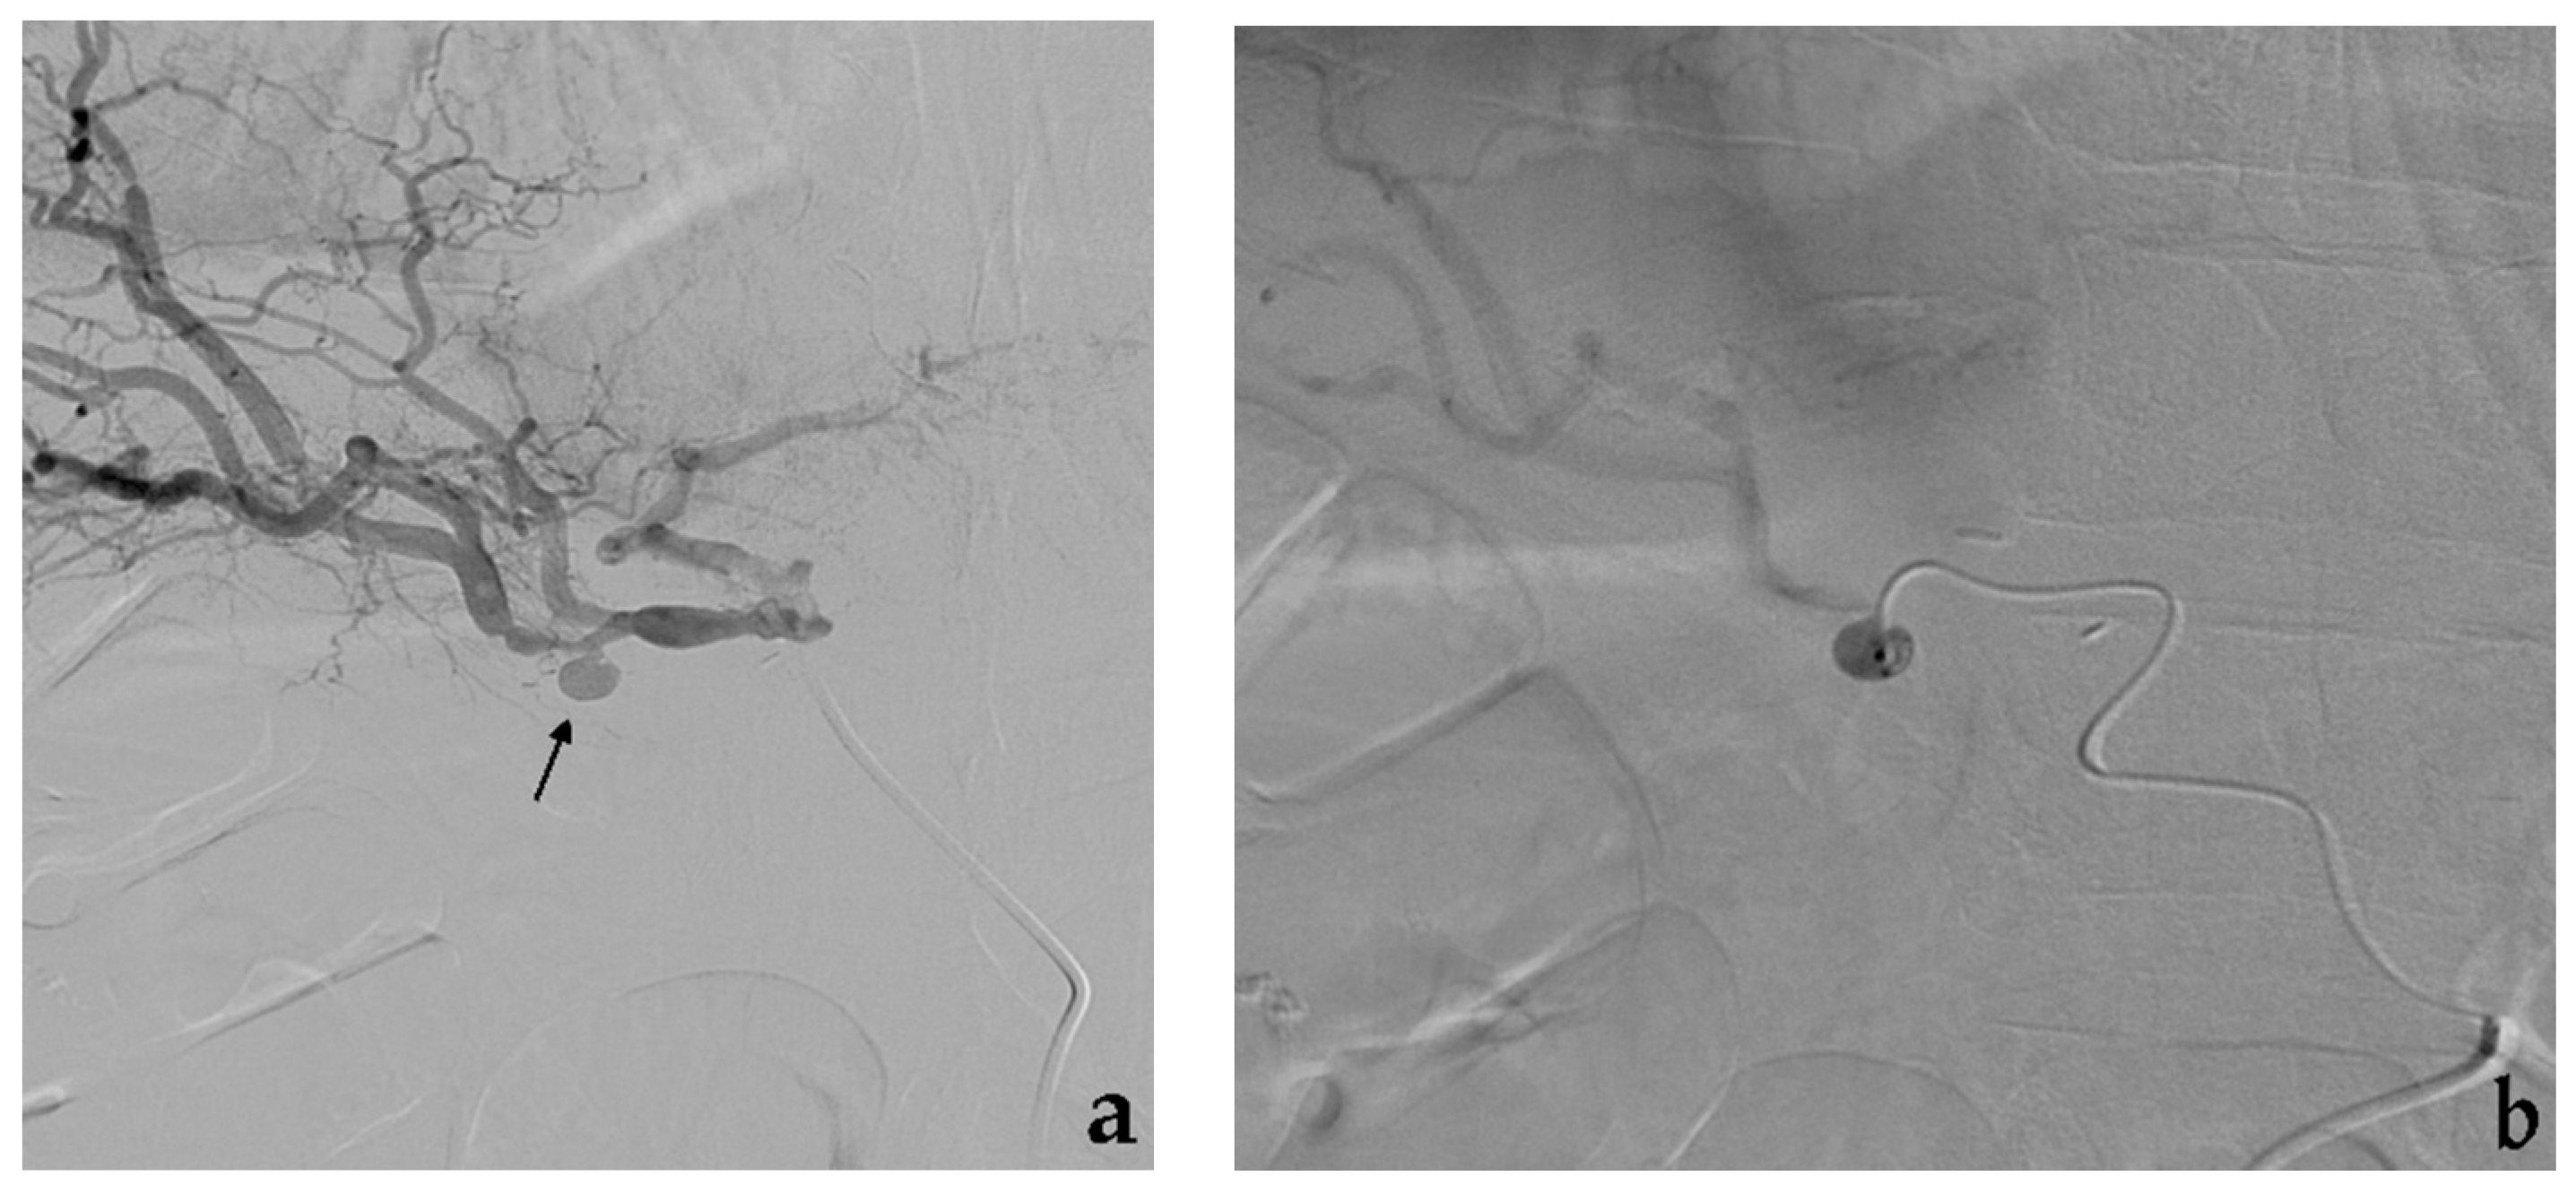

- Secco, G.; Chevallier, O.; Falvo, N.; Guillen, K.; Comby, P.O.; Mousson, C.; Majbri, N.; Midulla, M.; Loffroy, R. Packing technique with or without remodeling for endovascular coil embolization of renal artery aneurysms: Safety, efficacy and mid-term outcomes. J. Clin. Med. 2021, 10, 326. [Google Scholar] [CrossRef]

- Ma, T.; He, Y.; Zhong, W.; Luo, G.; Li, Q.; Wang, Z.; Zhang, H.; Wu, Z.; Qiu, C. Mid-term results of coil embolization alone or stent-assisted coil embolization for renal artery aneurysms. Ann. Vasc. Surg. 2021. [Google Scholar] [CrossRef]

- Bracale, U.M.; Narese, D.; Ficarelli, I.; De Laurentis, M.; Spalla, F.; Dinoto, E.; Vitale, G.; Solari, D.; Bajardi, G.; Pecoraro, F. Stent-assisted detachable coil embolization of wide-necked renal artery aneurysms. Diagn. Interv. Radiol. 2017, 23, 77–80. [Google Scholar] [CrossRef] [PubMed]